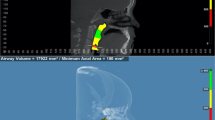

The airway was segmented using thresholding-based segmentation manually corrected slice by slice. The upper limit of oropharyngeal airway was set as a plane passing through posterior nasal spine (PNS) and parallel to coronal reference plane defined as PNS plane. The lower limit was set as a plane passing through the middle point of odontoid process of second cervical vertebra (OdP) and parallel to axial reference plane defined as OdP plane. The limits of the oropharyngeal volume are shown in Figure 4.

Segmented airway and landmarks were then exported respectively in stereolitographic (.stl) and IGES (.igs) files. Segmentation and computing the airway is part of a previous study [13].

The oropharyngeal airway volume and landmarks files were imported in Rhinoceros Software (Robert McNeel & Associates, Seattle, WA, USA) where a logarithmic sequence built for this purpose automatically computed planes and oropharyngeal volume.